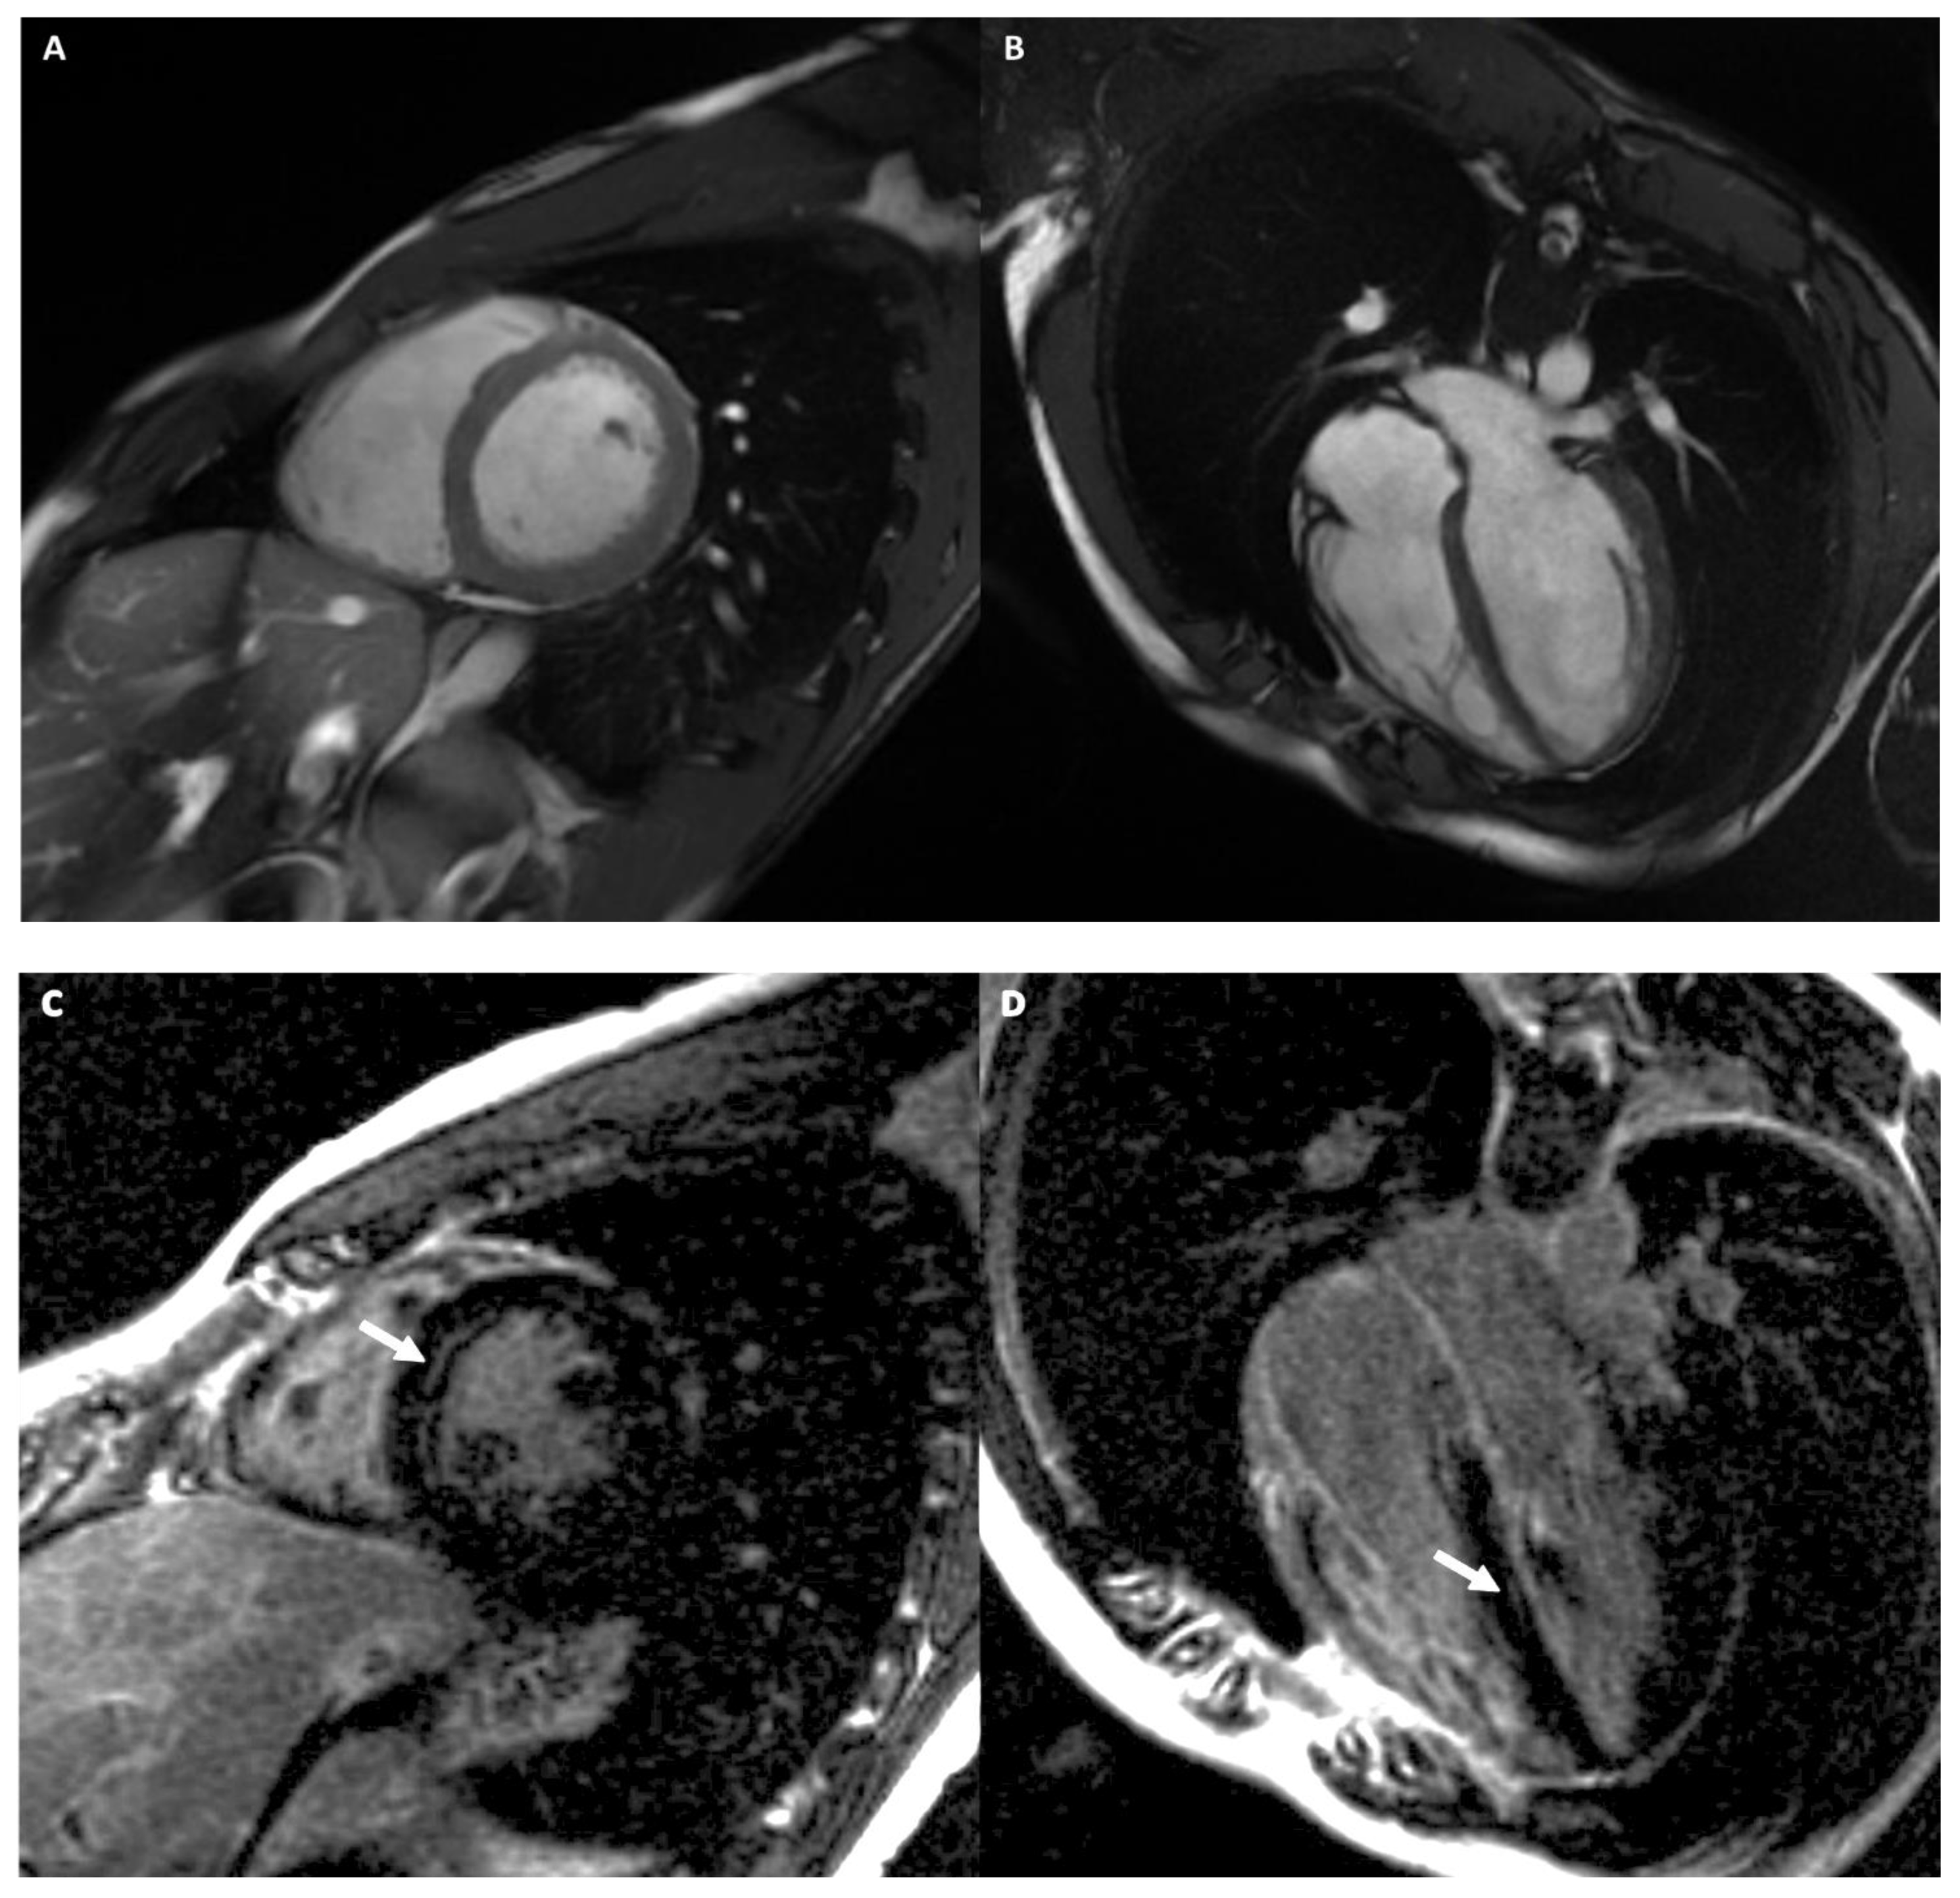

2.4. Mapping

2.4.1. T1 Mapping

2.4.2. T2 Mapping

2.5. Extracellular Volume Fraction